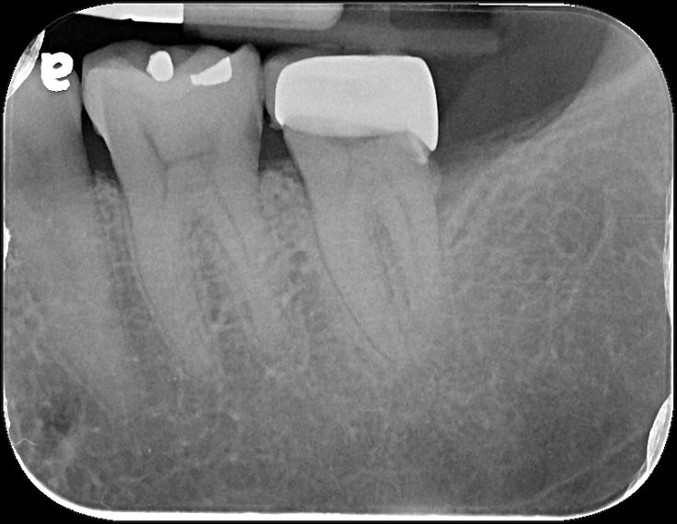

治療前,有銀粉復形,牙齒敏感

治療前,牙髓已接近被侵犯